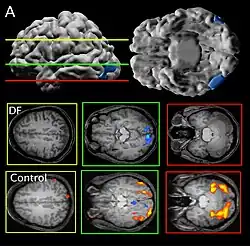

Her agnosia is thought to be caused by a bilateral lesion to her lateral occipital cortex, an area thought by dual-stream proponents to be the ventral "object recognition" stream.[1]

Patient DF's brain damage resulted from hypoxia due to accidental carbon monoxide poisoning in 1988, when she was 34 years old.[2] The lateral occipital cortex (LOC) in her brain is severely damaged and shows no activation presented with line drawings of common objects where healthy people usually do. Moreover, there is a reduction of white matter connections between LOC and other areas.[3] There is also some shrinkage in the intraparietal sulcus, often implicated in the dorsal stream for visuomotor control. The fusiform face area is intact. This would suggest the problem in DF's perception is disconnectivity between higher and lower order functioning.[4]

Recent MRIs have shown many enlarged sulci, like the intraparietal sulcus, parieto-occipital sulcus, and left calcarine sulcus, indicating atrophy.[4] Her visual field remains intact up to 30 degrees.[1]

DF does not benefit from haptic feedback—allowing her to pick up an object does not let her better estimate its width next time.[5] DF also does not use visual information about her grasp: when she can only see her grip in a distorted mirror, her performance does not change.[4] Consistent with all of this, brain imaging has shown no response to line drawings in her ventral stream. Furthermore, according to fMRI studies, the intraparietal sulcus showed preference for grasping motions over reaching motions—actually grabbing an object, in both DF and control patients, activates the intraparietal sulcus more than reaching.[4]